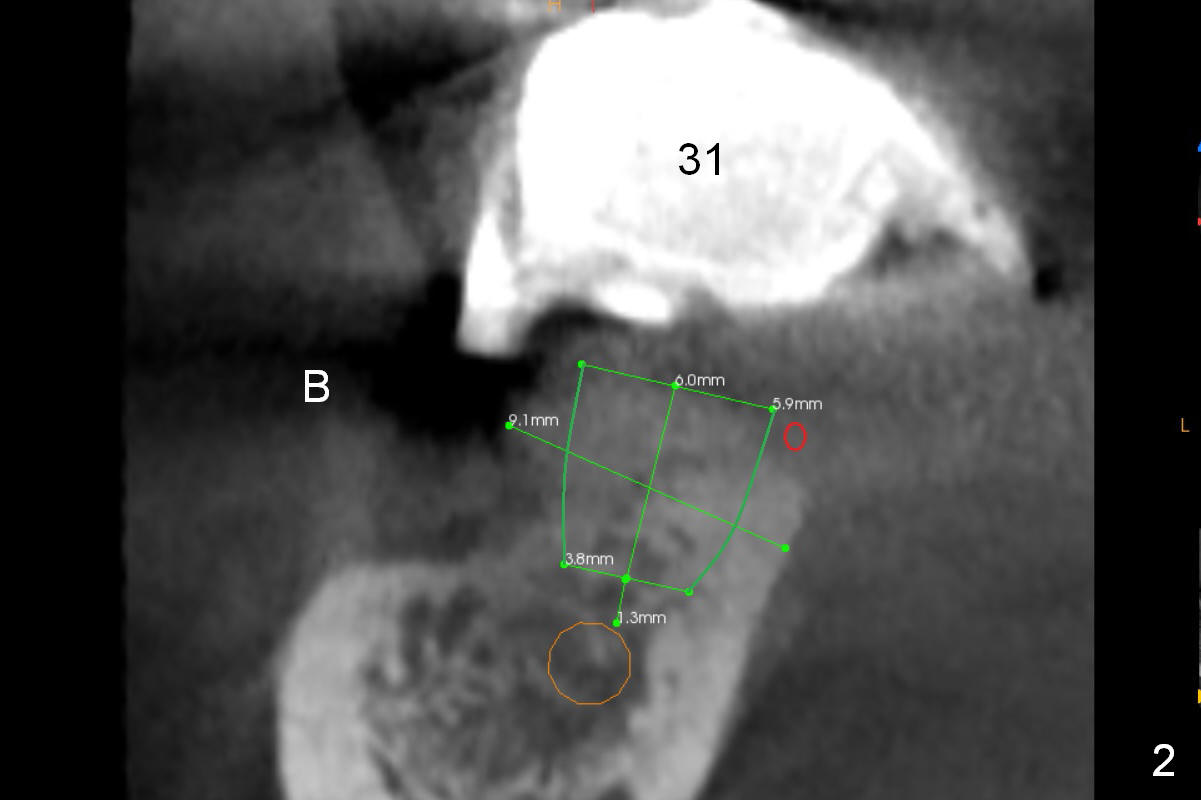

The patient wants to change unstable complete dentures to fixed ones. Because the problem of pain is associated with the lower left (Fig.1 the left Inferior Alveolar Nerve is more superficial), the lower arch will be reconstructed first. Totally 6 implants will be placed for bridges/crowns. Due to time constraint, four implants are placed at the 1st stage (#21, 22, 27 and 28 (Fig.4,5,8,9)); the lower denture will be retained immediately by ball abutments and soft relined. Two to three months later, two more implants will be placed (at #31 and 20, Fig.2,10). Note severe atrophy of the crest at #18 and 19 (Fig.11 and 12). If primary stability is achieved, a fixed immediate provisional will be fabricated.

In contrast to the upper arch, the bone density in the lower arch is high. The challenge is bone height. Short implants will be used (6 mm for #31 (Fig.2) and 8 mm for the majority of the others (at premolar and canine sites). If needed, extra implants will be placed at incisor sites (Fig.6,7 (implant can be longer)) and at #29 (Fig.3) . If a site is too small for a 3.8 mm 2-piece implant, a 1-piece one may be placed.